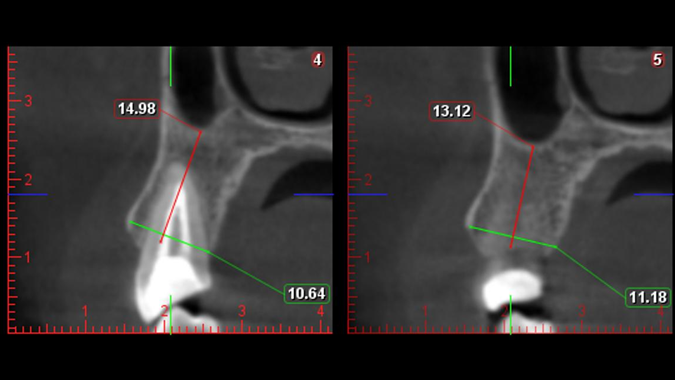

Clinical case: Digital Data Save concept in upper jaw premolar area

- Courtesy of Dr. Lysov Alexander Dmitrievich & Dr. Sofronov Matvey Vitalievich, Russia -

Keywords

AnyRidge, R2GATE, R2GATE guide, ISQ value, initial stability, immediate loading, KnifeThread, maxillary posterior, #14, Digital, Dr. Lysov Alexander Dmitrievich, Dr. Sofronov Matvey Vitalievich, zirconia abutment, CAD/CAM crown

“AnyRidge & R2GATE show stable results

after immediate extraction, immediate implant placement, & immediate loading,

even with low bone density.”